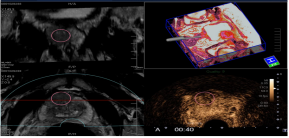

6. 智能融合&智能导航技术(Smart Fusion&Smart Navigation):智能融合技术可实现先前检查所获取的超声容积数据与实时2D超声图像之间的自动位置匹配,可用于介入治疗评估;也有CIVCO omniTRAX装置,实现超声图像和CT/MRI图像之间的自动位置匹配。

智能导航:利使用装有传感器的穿刺针,在超声图像上叠加穿刺针导航引导线,模拟显示穿刺针的路径和针尖的位置来实现导航,实时双屏幕针道显示,临床上利于穿刺介入。